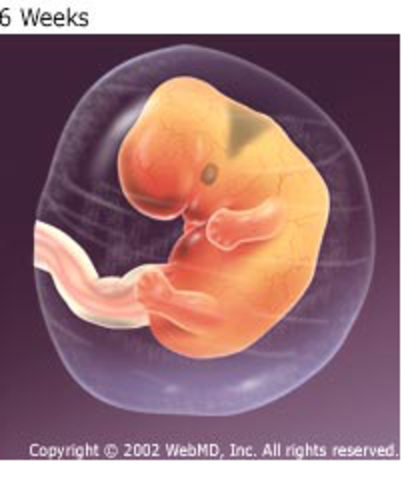

• Month 2 week 5-8

Month 2 week 5-8

The baby is still tiny but it's heart , brain , spinal cord , muscle and bones are beginning to develop